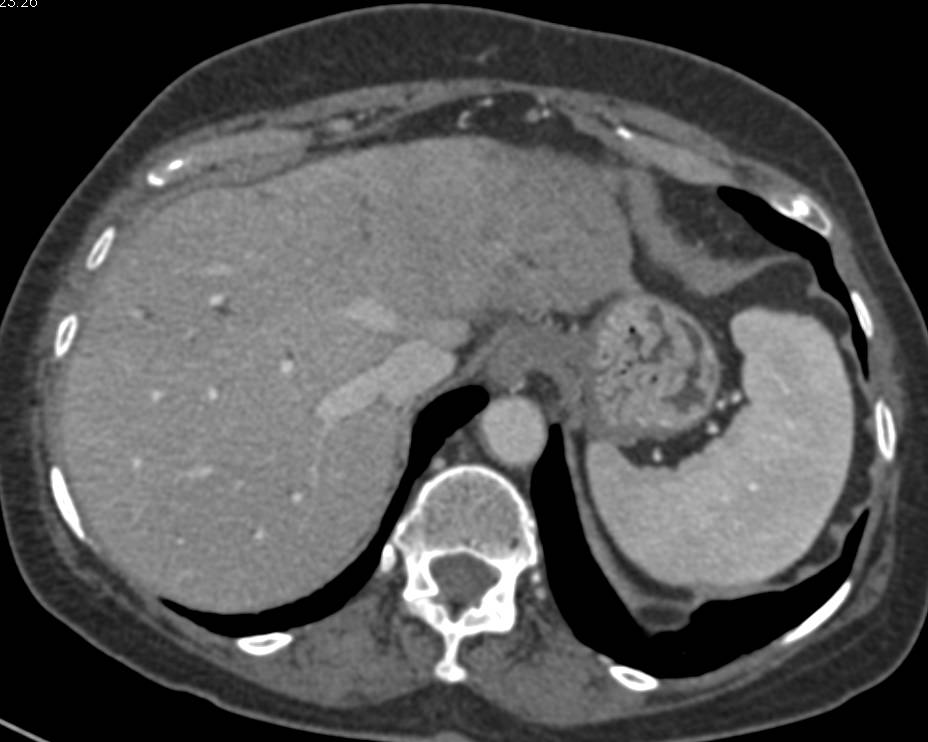

Что такое холангиокарцинома: симптомы и лечение